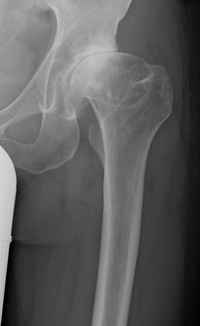

Morbus Perthes

Morbus Perthes, Morbus Legg-Calve-Perthes, Osteochondrosis deformans coxae juvenilis, juvenile Hüftkopfnekrose, idiopathische kindliche Hüftkopfnekrose. Erkrankung des Hüftkopfes im frühen Kindesalter.

Bei der von der Entstehung her als Osteochondronekrose eingestuften Erkrankung kommt es zu einem Zerfall und späteren Wiederaufbau der Hüftkopfkappe des betreffenden Hüftgelenkes.